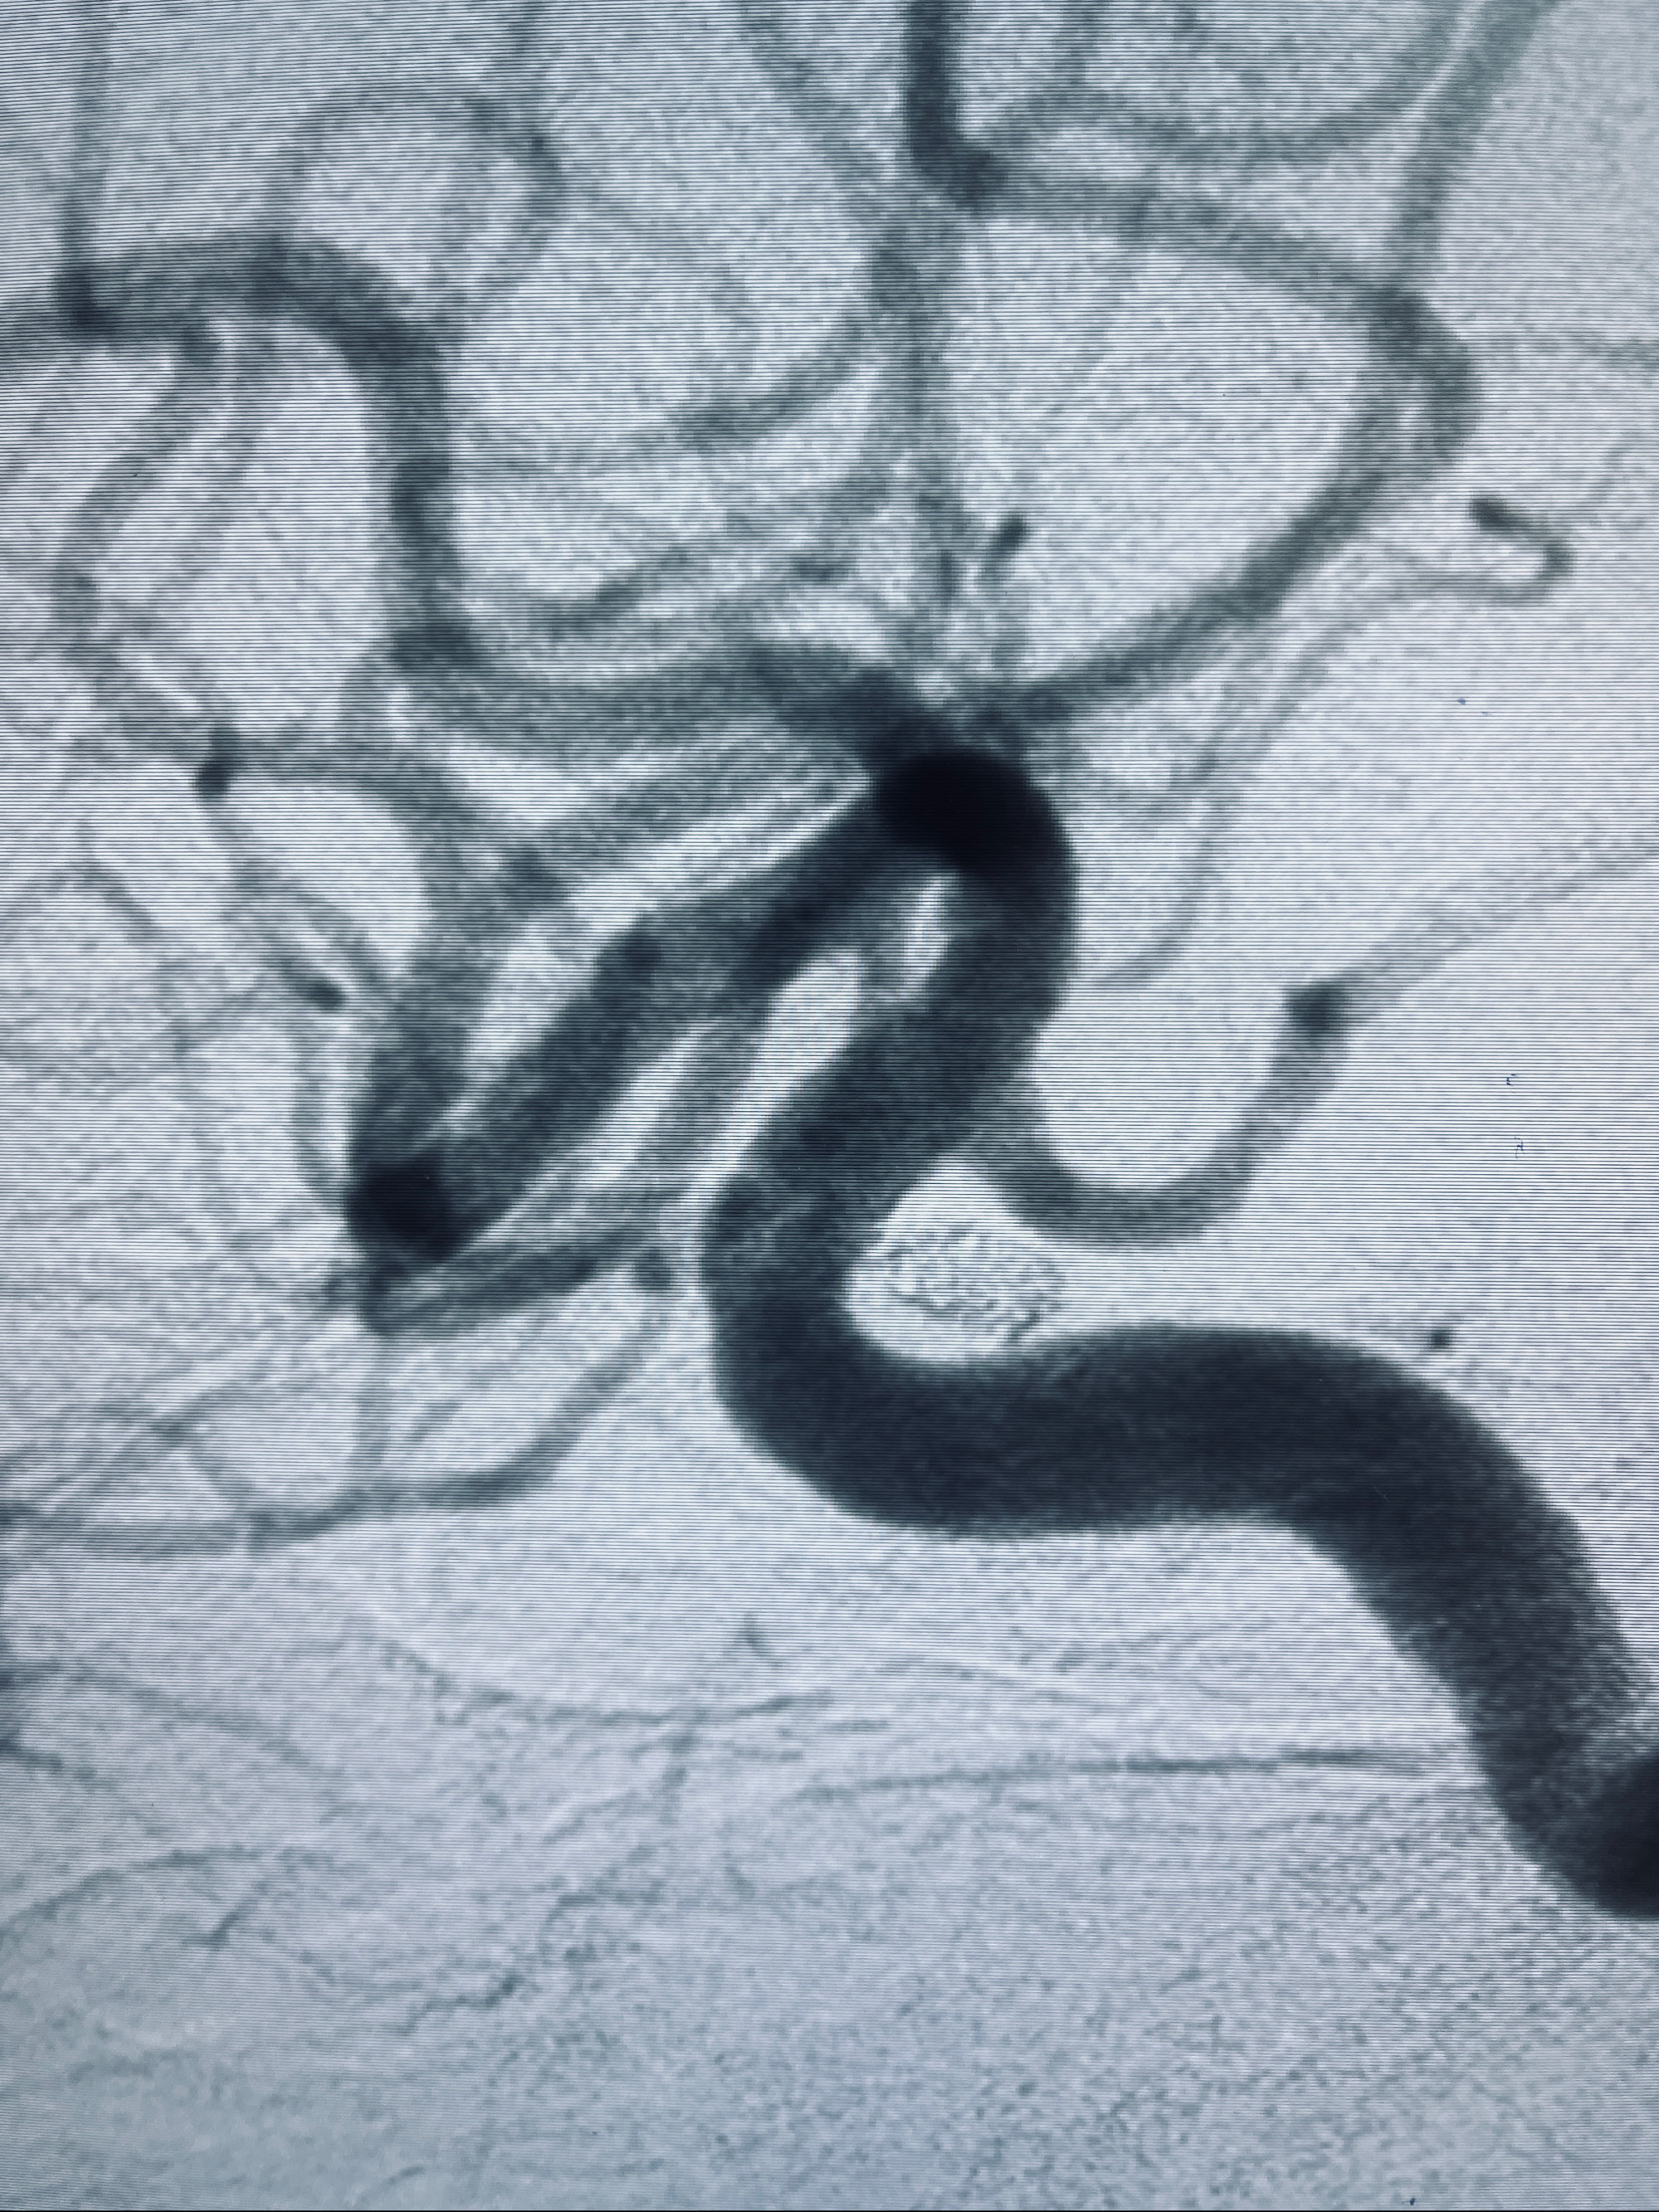

2022-09-29复查DSA